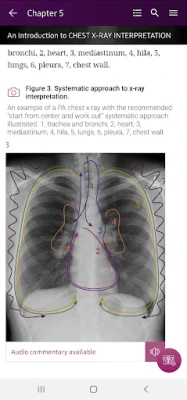

Section III* starts with a chapter on how to interpret the chest x-ray; this is where you begin to put your new knowledge into practice. Now that you know what to look for, you can do so in a systematic way to ensure the accurate identification of pathology.

How To’s – 34 step-by-step guides, with annotated x-rays, to illustrate key skills needed to confidentially interpret chest x-ray.

Radiological Anatomy – Descriptions of various anatomical structures as they would appear on PA and lateral chest x-rays.